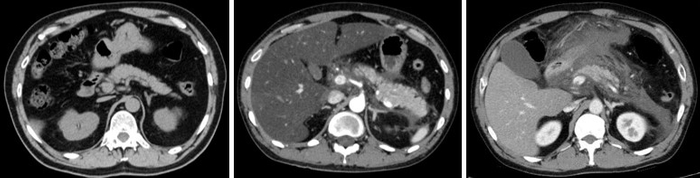

研究グループは、自分たちの先行研究をもとに、セルレイン※4 という分子をマウスに繰り返し投与して急性膵炎を誘導しました。この急性膵炎モデルマウスに対して、まずはLRRK2を特異的に抑制する阻害薬を投与すると、膵炎を引き起こす炎症性サイトカイン※5 反応が低下し、急性膵炎が軽症化することが分かりました。また、全身の細胞にLRRK2が強く発現し、LRRK2の機能が活性化しているLRRK2トランスジェニックマウス(LRRK2 Tgマウス)に膵炎を誘導したところ、阻害薬投与の場合とは逆に、炎症性サイトカイン反応が増加し、急性膵炎が重症化することが判明しました。ここから、LRRK2の機能亢進と低下が、それぞれ膵炎の重症化と軽症化に関与することを発見しました。

膵炎の発症には、腺房細胞※6 と免疫細胞の両方が関わることが知られています。どちらの細胞のLRRK2が影響を及ぼしているかを検証するため、LRRK2 Tgマウスと野生型マウスを用いて骨髄移植※7 実験を行いました。その結果、免疫細胞であるマクロファージ・樹状細胞※8 のLRRK2が、急性膵炎の重症化に必須であることが分かりました。

さらに、急性膵炎の重症化に、細菌と真菌のどちらがより影響するか検証するため、腸管内の細菌と真菌をそれぞれ抗細菌薬と抗真菌薬で除去し、症状の変化を確認しました。その結果、抗細菌薬による細菌の除去はLRRK2 Tgマウスの膵炎の重症度に影響を与えず、抗真菌薬による真菌の除去により、膵炎は著しく軽症化しました。さらに、重症膵炎を発症したLRRK2 Tgマウスの膵臓のマクロファージ・樹状細胞は、細菌成分ではなく真菌成分に反応し、炎症性サイトカインを多く産生しました。